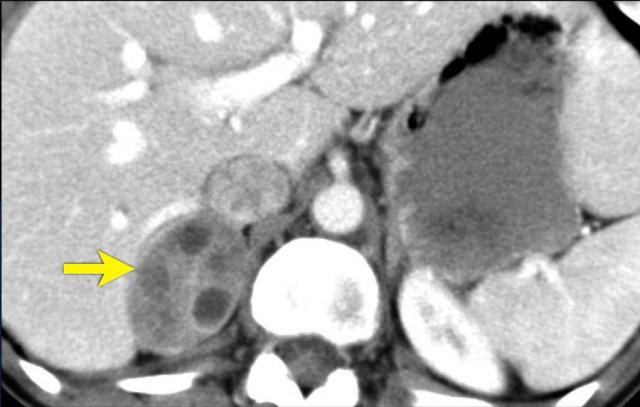

U tủy mỡ (Myelolipoma)

U tủy mỡ là các khối u lành tính cấu thành từ các thành phần tủy xương.

Thông thường chúng dễ nhận biết trên CT hoặc MRI vì chứa các vùng mỡ đại thể.

Vôi hóa gặp trong 24% các trường hợp.

Khối tuyến thượng thận thấy trên CT ở đây chứa mỡ đại thể, đặc hiệu cho chẩn đoán u tủy mỡ.

Hình ảnh CT của một khối tuyến thượng thận khác chủ yếu cấu thành từ mỡ đại thể.

Chẩn đoán: u tủy mỡ.